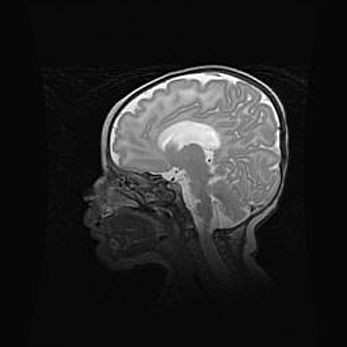

Мальформация Денди-Уокера. Киста задней черепной ямки.

Агенезия мозолистого тела.

Возраст: 2,5 месяца

Вес: 2420 г

Пол: женский

Окружность головы: 37 см

Срок гестации: 32 недели

Мальформация Денди—Уокера — редкий вид патологии ЦНС, представляющий собой врожденный порок развития каудального отдела ствола и червя мозжечка, ведущий к неполному раскрытию срединной (Мажанди) и латеральных (Лушка) апертур IV желудочка мозга. Для этогно синдрома характерна триада симптомов: гипотрофия червя мозжечка и/или полушарий мозжечка, кисты задней черепной ямки, гидроцефалия различной степени. В 70% случаев порок сочетается и с другими аномалиями головного мозга, в частности с агенезией мозолистого тела.